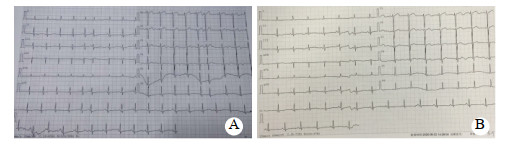

1 资料与方法患者66岁,男性,农民,2020年6月15日下午饮酒(量不详)后误服“虫螨腈”30~50 mL,后昏睡不醒,次日醒酒后出现恶心、呕吐非咖啡渣样胃内容物1次,腹泻3次,为稀水样便,总量少,伴心悸、气促、出汗,无胸闷、胸痛、腹痛,无发热、肌肉酸痛、肌颤、抽搐,家属急送双柏县人民医院急诊科就诊。既往体健,无高血压、糖尿病、心脏病、肺部疾病、外伤等病史。查体:体温36.5℃,心率86次/min,呼吸20次/min,血压102/67 mmHg(1 mmHg=0.133 kPa),血氧饱和度95%(未吸氧);GCS评分15分;全身皮肤出汗,双侧瞳孔等大等圆,直径2.5 mm,光反射灵敏;口唇无发绀;颈软无抵抗,两肺呼吸音清晰,未闻及干湿性啰音;心律齐,未闻及杂音;腹平软,无肌紧张,无压痛及反跳痛,肝脾未触及,肠鸣音正常;双下肢无浮肿,四肢肌力、肌张力正常,病理征未引出。入院后予急诊留观处理,予“奥美拉唑、果糖二磷酸钠、环磷腺苷葡胺、维生素C、维生素B6、氯化钾”静滴及补液对症治疗。心电图示窦性心律,ST-T正常。相关辅助检查见表 1。患者治疗第2天,腹泻缓解,无呕吐发生,正常进食,小便正常。治疗3 d后(6月19日)患者心悸、气促加重,伴大量出汗,收住ICU治疗。查体:体温36.7℃,心率117次/min,呼吸21次/min,血压107/66 mmHg,血氧饱和度95%(鼻导管吸氧3 L/min);GCS评分15分;全身皮肤出汗较多,余无特殊改变。心电图示窦性心律,偶发房性期前收缩,T波低平,见图 1A。肺CT示双肺多发纤维增殖灶,慢性支气管炎,肺气肿,双肺多发肺大疱,见图 2A~B。入住ICU后的相关辅助检查见表 1。继续予上述治疗,并予“地塞米松磷酸钠注射液10 mg/d”静脉注射。经治疗,患者心悸、气促无明显缓解,仍有大量出汗,6月22日转至本院急诊科进一步诊治。查体:体温37.2 ℃,脉搏94次/min,呼吸27次/min,血压103/58 mmHg,血氧饱和度94%(鼻导管吸氧3 L/min);GCS评分15分;全身大汗淋漓,全身皮肤黏膜完好,无破溃,双侧瞳孔等大等圆,直径2.5 mm, 光反射灵敏;口唇无发绀;呼吸急促,心肺腹查体无异常;四肢肌肉无挤压痛,四肢肌力、肌张力正常,病理征未引出。心电图示窦性心律,T波低平,见图 1B。测随机血糖为5.9 mmol/L。肺CT与前相仿,见图 2C~D。相关辅助检查见表 1。本病例资料报道已获得患者家属的知情同意。

| A:窦性心律,偶发房性期前收缩,T波低平(2020-06-19);B:窦性心律,T波低平(2020-06-22) 图 1 患者心电图检查结果 |